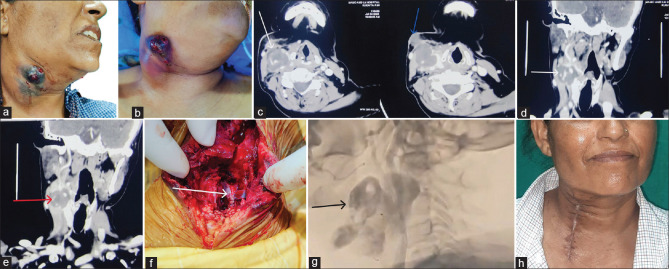

Rationale and patient concerns: A 50-year-old female admitted with right neck swelling and fever was initially diagnosed with infective cervical lymphadenopathy accompanied by internal jugular vein thrombosis for which broad-spectrum antibiotics and anticoagulants were started.

Diagnosis and treatment: A few days later, she developed right common carotid pseudoaneurysm with sentinel bleed which was further managed by common carotid artery repair with the help of pericardial allograft by cardiothoracic vascular surgery and ear, nose and throat team.

Outcome and take-away lessons: This report emphasises the need of having a high index of suspicion for Lemierre's syndrome and its unusual presentation, as well as a multidisciplinary approach to addressing both venous and arterial complications associated with this entity and achieving outstanding results.